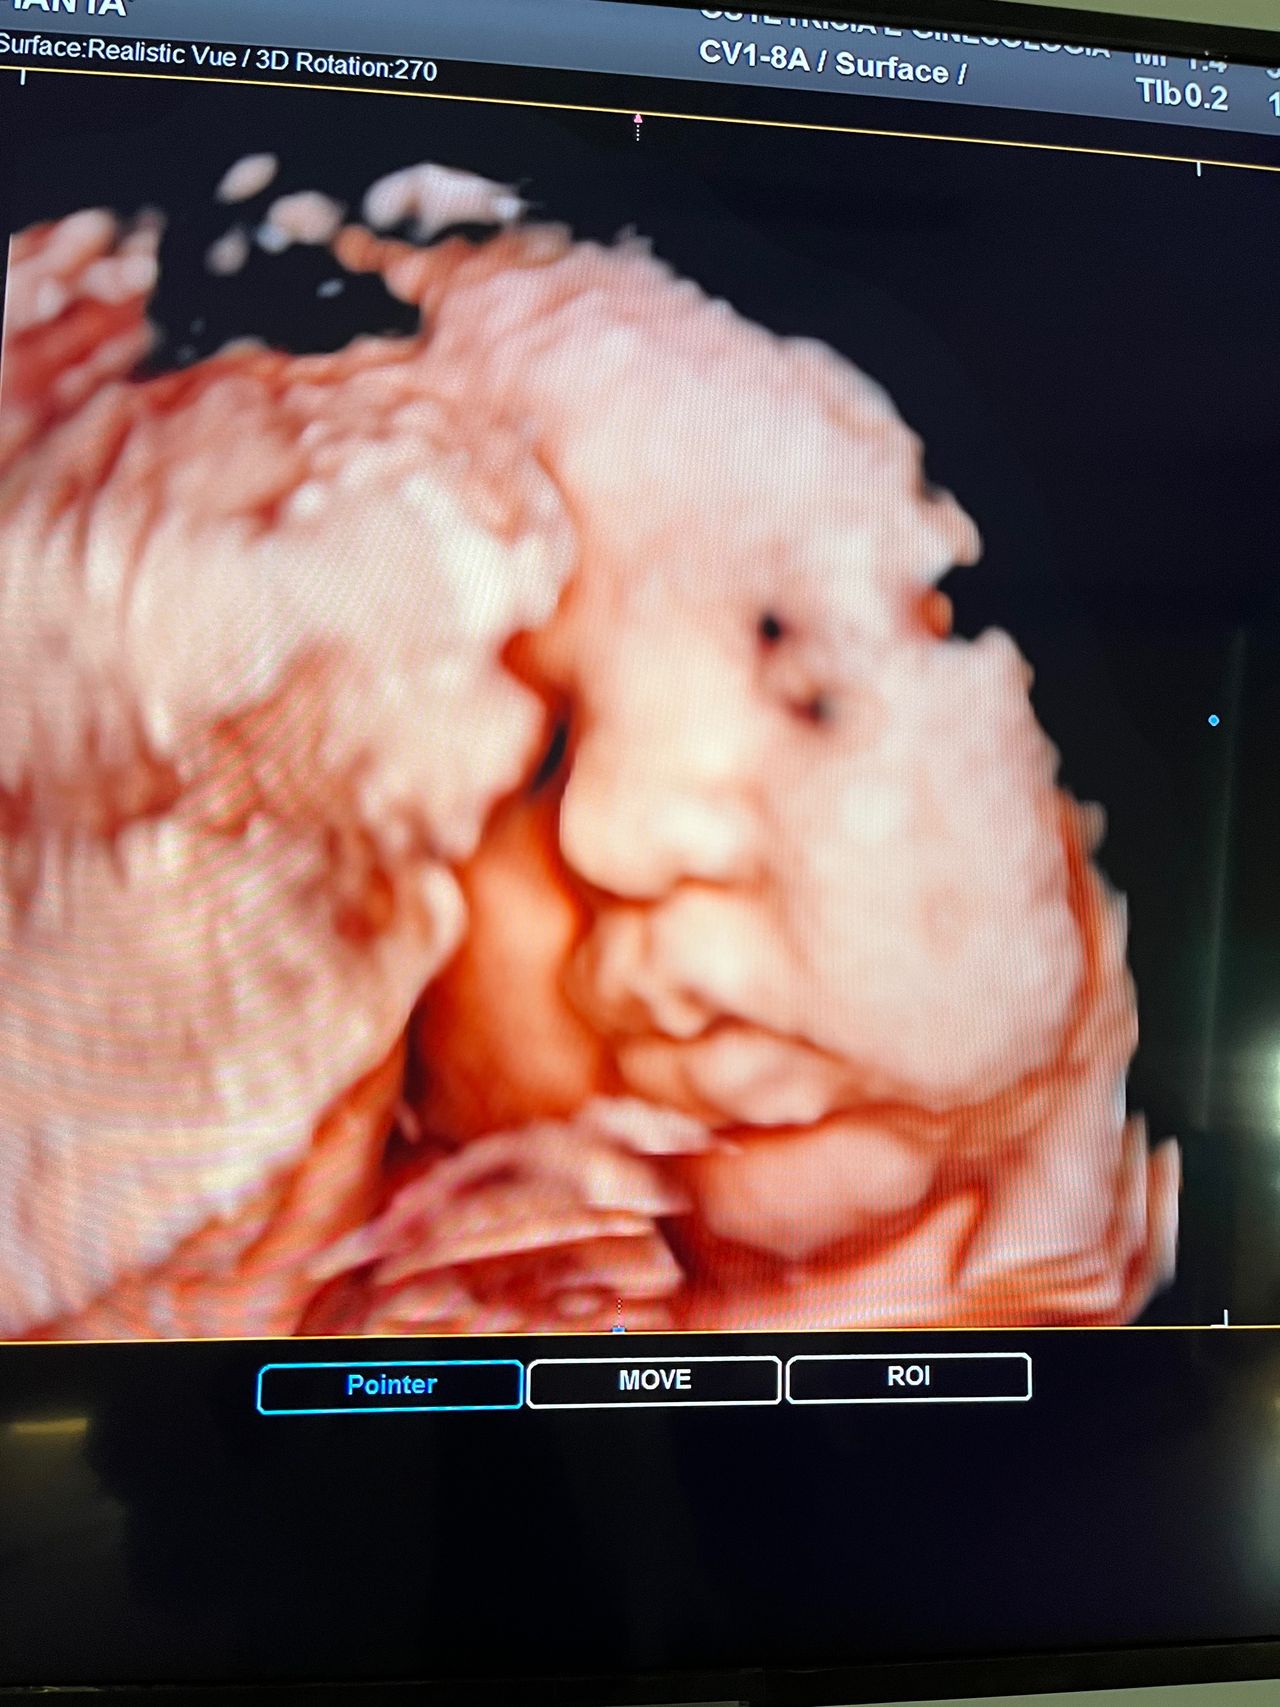

Attualmente lavoro come Dirigente medico nella SC di Ostetricia e Ginecologia dell'Ospedale Michele e Pietro Ferrero di Verduno, mi occupo prevalentemente di screening prenatale, ecografia ostetrica del I trimestre( misurazione translucenza nucale,NT), ecografia morfologica del II trimestre, ambulatorio pregresso taglio cesareo, ecografia ostetrica 3D. Seguo le gravidanze fisiologiche e quelle ad alto rischio , presto servizio in sala parto. Eseguo visite ginecologiche di I-II livello in regime ambulatoriale, counseling contraccettivo ed eventuale prescrizione pillola, inserimento spirale (IUD), dispositivo sottocutaneo (Nexplanon).

Foto e video